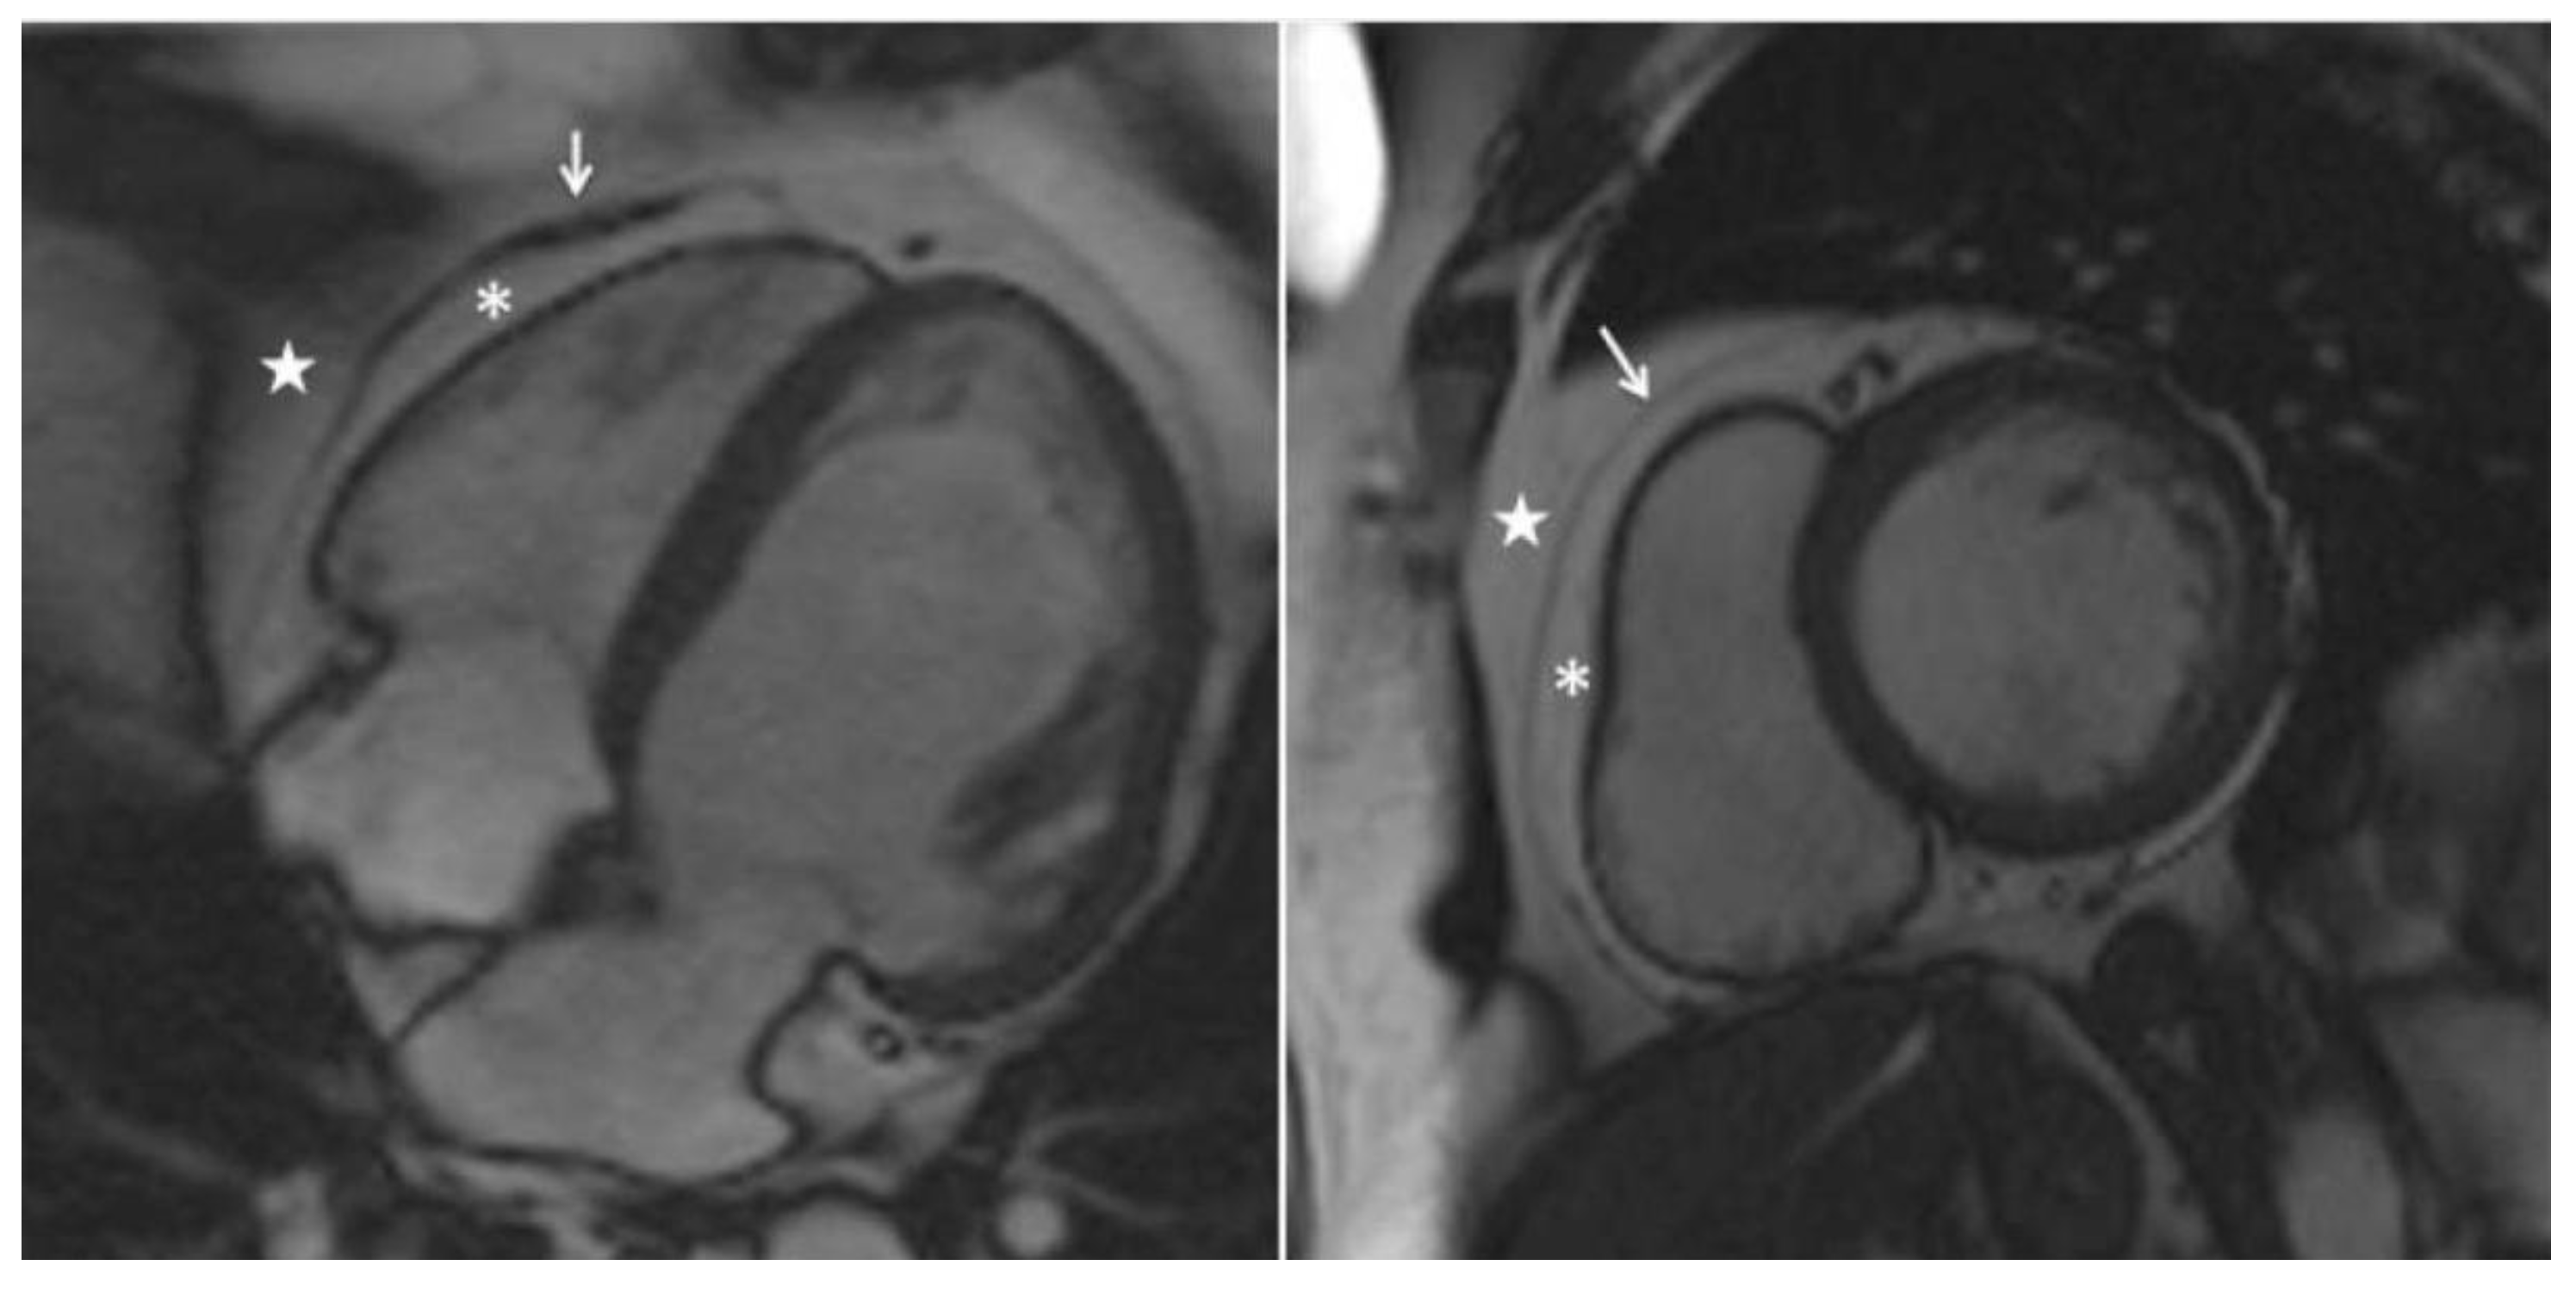

- Chen, S.; An, D.; Feng, C.; Bian, Z.; Wu, L.M. Segmentation of Pericardial Adipose Tissue in CMR Images: A Benchmark Dataset MRPEAT and a Triple-Stage Network 3SUnet. IEEE Trans Med Imaging. 2023, 42, 2386–2399. [Google Scholar] [CrossRef]

- Daudé, P.; Ancel, P.; Confort Gouny, S.; et al. Deep-Learning Segmentation of Epicardial Adipose Tissue Using Four-Chamber Cardiac Magnetic Resonance Imaging. Diagnostics. 2022, 12, 126. [Google Scholar] [CrossRef]

- Kulasekara, M.; Dinh, V.Q.; Fernandez-del-Valle, M.; Klingensmith, J.D. Comparison of two-dimensional and three-dimensional U-Net architectures for segmentation of adipose tissue in cardiac magnetic resonance images. Med Biol Eng Comput. 2022, 60, 2291–2306. [Google Scholar] [CrossRef]